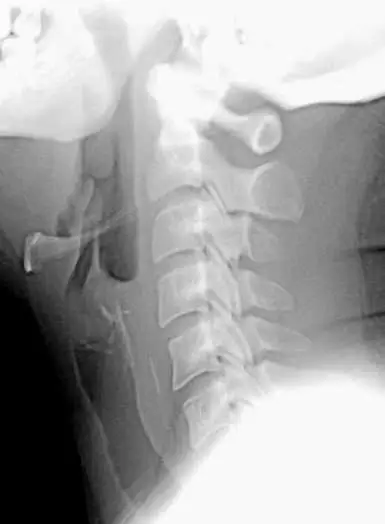

一中年男性晚飯後出現喉痛、吞嚥困難等症狀就診,頸部 X光如下圖,下列敘述何者正確?

X 光為頸部側位軟組織攝影,可見一條線狀放射性高密度異物(疑似魚骨或尖銳食物骨片)投影於第五、第六頸椎水平,位置位於喉部及食道入口交界處(upper esophageal sphincter/cricopharyngeal region)後方,與氣管、甲狀軟骨及會厭無重疊放射性高密度影。

此異物位置過低,非停留於會厭軟骨(epiglottic cartilage,約第三頸椎水平)處,顯示異物已進入咽後空間並卡在食道入口,因此需要以內視鏡取出,而非僅在喉部做異物移除。

選項A 「頸部 X 光可見異物位於會厭軟骨處」

會厭軟骨位於第三頸椎水平,且其本身並不呈放射性密度。影像中異物出現在第五、第六頸椎水平、且屬高密度異物,與會厭軟骨位置不符。此選項錯誤。 -